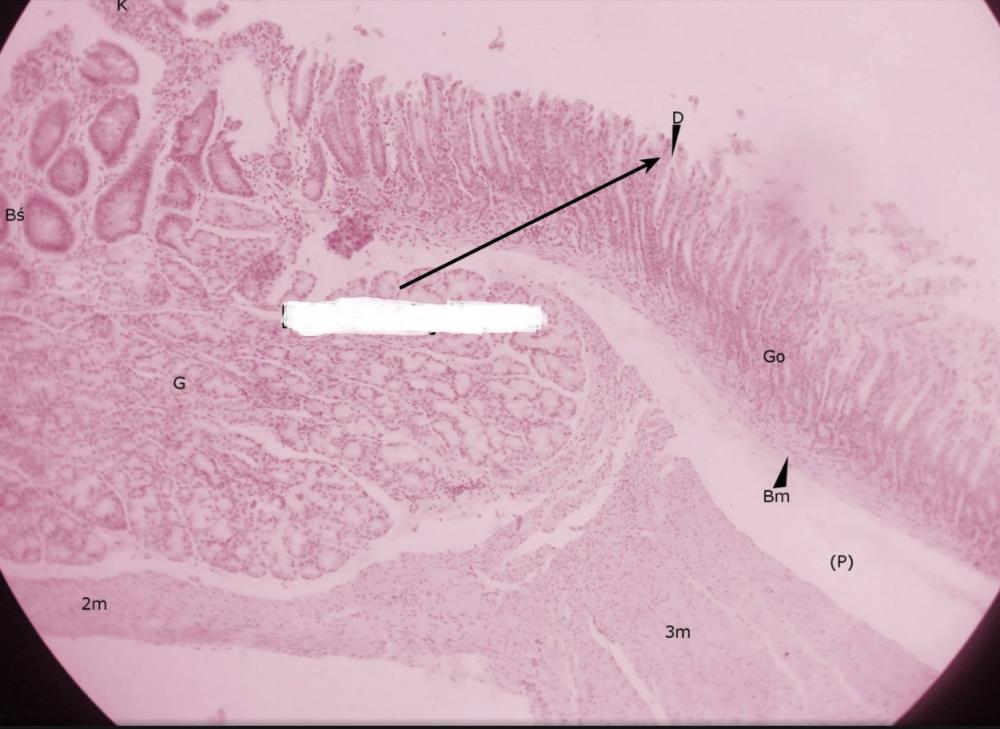

dołki żołądkowe (przejście żołądka w dwunastnicę)

pólka żołądkowe (przejście żołądka w dwunastnicę)

rozgałęzione gruczoły cewkowe - odźwiernikowe (przejście żołądka w dwunastnicę)

kosmek jelitowy (przejście żołądka w dwunastnicę)

krypta jelitowa (przejście żołądka w dwunastnicę)

gruczoły Brunnera (przejście żołądka w dwunastnicę)

błona mięśniowa, składająca się z warstwy okrężnej o podłużnej (przejście żołądka w dwunastnicę)

miejsce po błonie podśluzowej (przejście żołądka w dwunastnicę)

blaszka mięśniowa błony śluzowej (przejście żołądka w dwunastnicę)

gruba, trójwarstwowa mięśniówka żołądka (przejście żołądka w dwunastnicę)